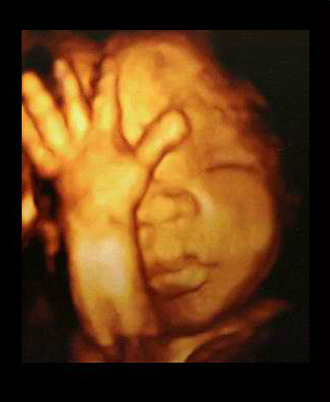

- 초기 정밀 초음파

- 4차원 후기 정밀 초음파 (26~28주)